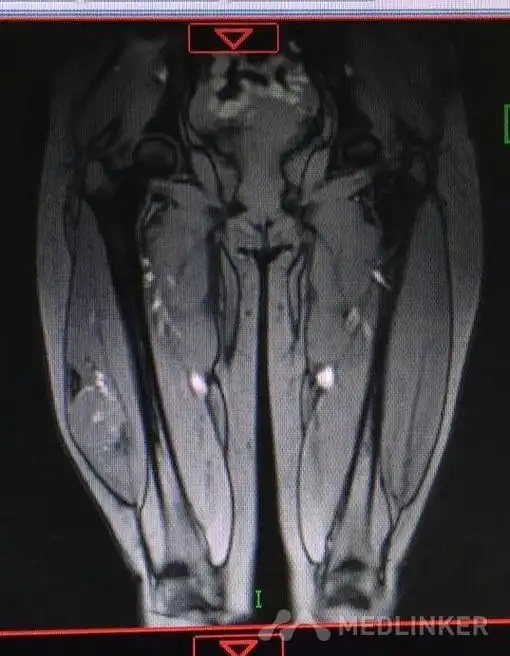

右大腿包块

随访 讨论腺泡状软组织肉瘤好发于青春期女性,多位于四肢深部肌肉或